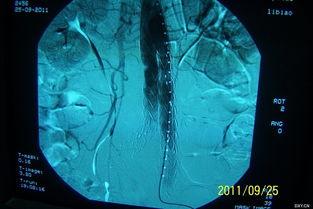

主动脉支架,听起来是不是很专业?没错,它是一种用于治疗主动脉夹层的医疗器械。主动脉夹层是一种严重的血管疾病,如果不及时治疗,后果不堪设想。而国产主动脉支架,就是用来修复受损的主动脉,防止病情恶化的“救星”。

视频中的案例让我印象深刻。有一位名叫李先生的病人,因为主动脉夹层导致生命垂危。在医生的建议下,他选择了国产主动脉支架进行治疗。经过一段时间的恢复,李先生的病情得到了明显改善,生活也恢复了正常。

这个案例充分说明了国产主动脉支架在临床治疗中的重要作用。事实上,国产主动脉支架已经广泛应用于国内外多家医院,为无数患者带来了希望。